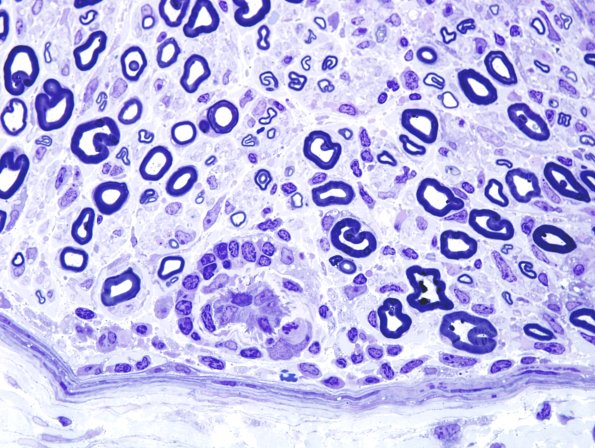

8A4 GBS (Case 8) Plastic 9

In this case an inflammatory perivascular infiltrate was particularly prominent. (Plastic sections)